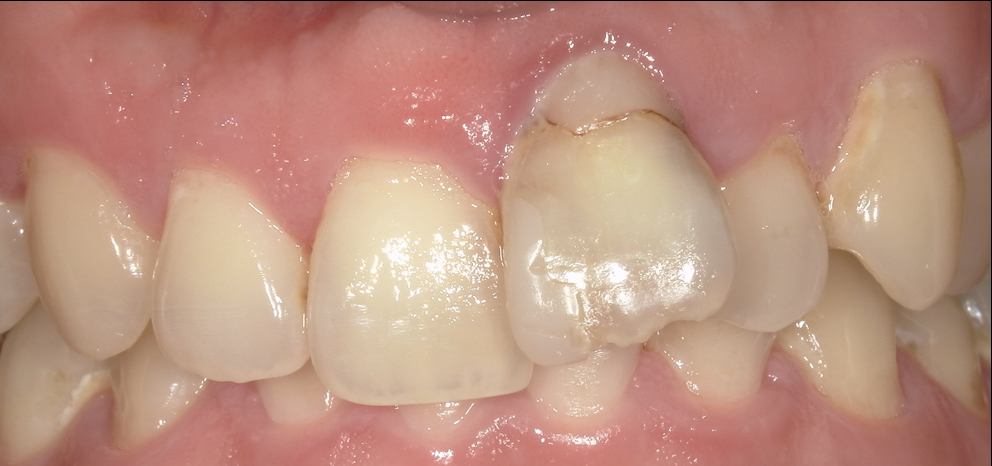

前歯1本だけのセラミック治療(シングルセントラル)|色・形・透明感を周囲に馴染ませたケース

- 担当医

- 生野誠

- 主訴

- 前歯が折れてとりあえずの仮歯を入れたままにしていた。

折れる可能性があるため部分矯正で引っ張り出さないといけないと言われた。

可能であればそのままやりたい

- 期間

- • 期間:2週間〜1ヶ月

• 回数:4回(カウンセリング含む)

- 費用

- セラミッククラウン(前歯1本):165000円(税込)

ファイバーコア:22000円(税込)

仮歯:16500円(税込)

- 治療内容

- 1. カウンセリング/写真・色合わせ(シェード)

2. 既存補綥物の除去・形成(必要最小限の切削を意識)

3. 精密印象(または口腔内スキャン)

4. プロビジョナル(仮歯)で形とラインを微調整

5. 技工士と情報共有(写真・シェード・マッピング)

6. セラミック装着(接着操作)→咬合・発音・清掃性を確認

使用材料

• オールセラミッククラウン(ジルコニア+レイヤリング )

- 治療に伴うリスク

- • セラミックは強い衝撃で欠ける/割れることがあります

• 歯ぎしり・食いしばりが強い場合、マウスピース(ナイトガード)を推奨します

• 失活歯(神経のない歯)の場合、時間とともに色調変化が出ることがあります

• 歯肉の状態や清掃状況により、歯ぐきのラインが変化することがあります